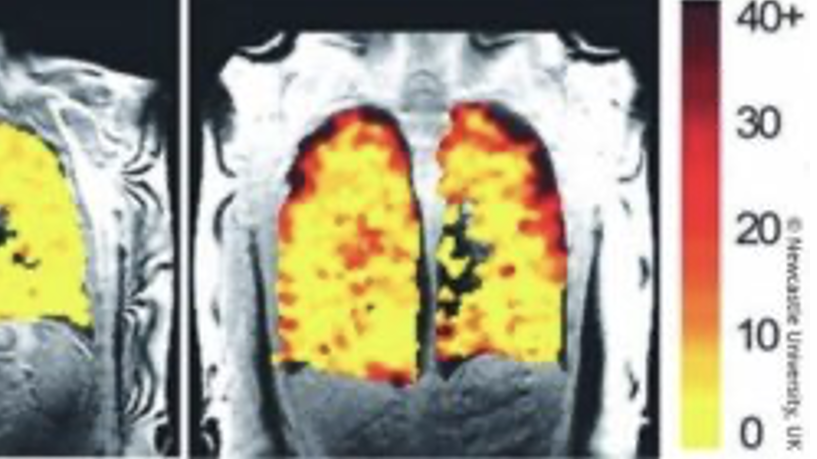

El método utiliza un gas especial, el perfluoropropano, que puede ser inhalado de forma segura por los pacientes. Una vez dentro de los pulmones, las resonancias magnéticas capturan cómo se dispersa el gas, identificando las áreas de ventilación efectiva y deficiente. Esto permite un análisis detallado de la función pulmonar, así como un seguimiento de los efectos de los tratamientos.

Después de inhalar un gas especial, las resonancias magnéticas capturan su dispersión a través de los pulmones, identificando áreas de ventilación efectiva y deficiente.

El profesor Pete Thelwall, director del Centro de Imágenes In Vivo de la Universidad de Newcastle, explica; “Nuestras exploraciones muestran dónde hay ventilación irregular en pacientes con enfermedad pulmonar y nos muestran qué partes del pulmón mejoran con el tratamiento. Por ejemplo, cuando escaneamos a un paciente mientras usa su medicamento para el asma, podemos ver qué parte de sus pulmones y qué partes de su pulmón son más capaces de mover el aire hacia adentro y hacia afuera con cada respiración”.